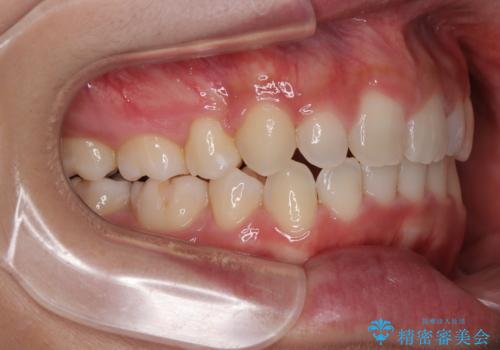

- 前歯のデコボコやクロスバイト、口元の突出感を気にして来院された患者様です。

上下左右の第一小臼歯4本を抜歯して、ワイヤー装置にて矯正治療を行うこととしました。

途中出産や育児があり、治療期間長くなってしまいましたが、ストレスなく唇が閉じられるような口元に仕上げることができました。